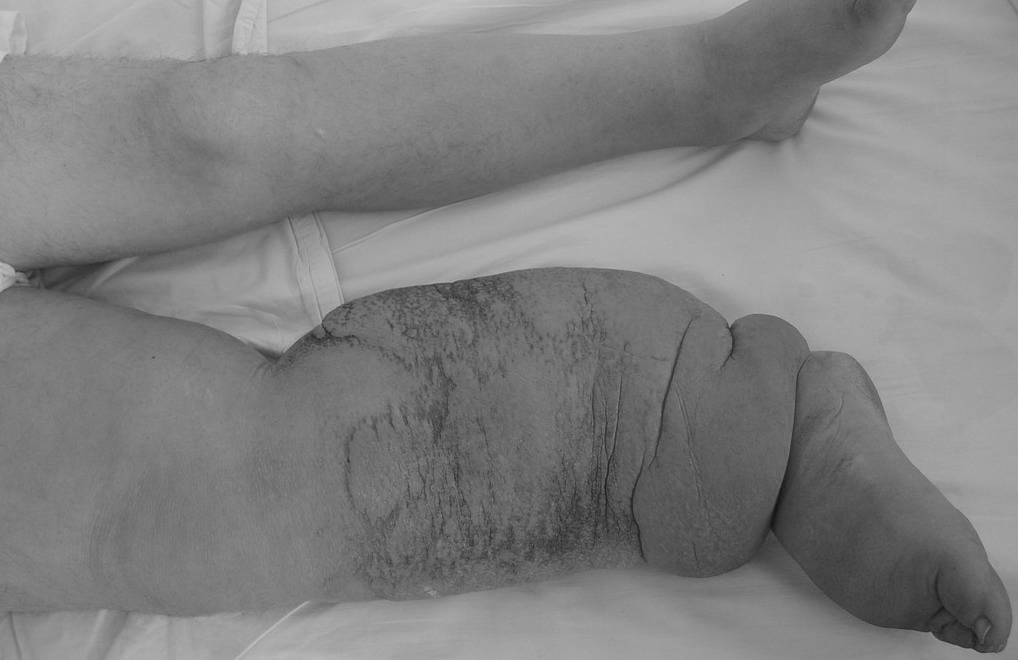

“几十年前,我还偶尔能看到这样一群病人,他们面黄肌瘦,明显看就是营养不良。但是,在那个时代,生活水平都普遍不好,消瘦的病人并不少见。但是,当我看到他们那好似大象的双腿,在地上艰难地拖动着,我知道我这辈子都不可能轻易忘记那一场景..."

因为丝虫感染淋巴系统等组织后,可以在里面“吃喝”“繁殖”,最终刺激局部皮肤增生,同时堵塞淋巴管,导致肿胀。

所以,远远的看,这些被感染的皮肤,就好似大象皮一样厚实。

班氏吴策线虫和马来布鲁线虫引起的丝虫病,也被称为象皮病或象皮肿。

这是因为此2种丝虫,可寄生在人的腿部、阴囊、臂部等皮肤的皮下组织、淋巴系统、腹腔或胸腔内,然后分泌因子刺激皮肤增厚,并堵塞淋巴管,导致淋巴肿大,最终形成厚如大象皮一样的组织。

实际上只有丝虫寄生在淋巴管,才能导致象皮病。